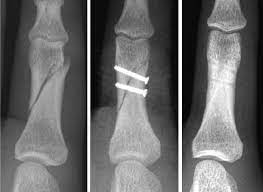

For fractures of the middle phalanx if conservative treatment is not sufficient then percutaneous pinning or open reduction using K-wires is used. Treatment principles for proximal and middle phalangeal fractures. Phalangeal fractures of the hand are a common injury that presents to the emergency department and clinic.

Middle phalangeal fractures proximal to the FDS insertion have an apex dorsal angulation whereas fractures distal to the FDS insertion have an apex volar angulation as shown in the figure. Undisplaced or minimally displaced fractures of the diaphysis of the middle phalanx can be treated non-operatively.